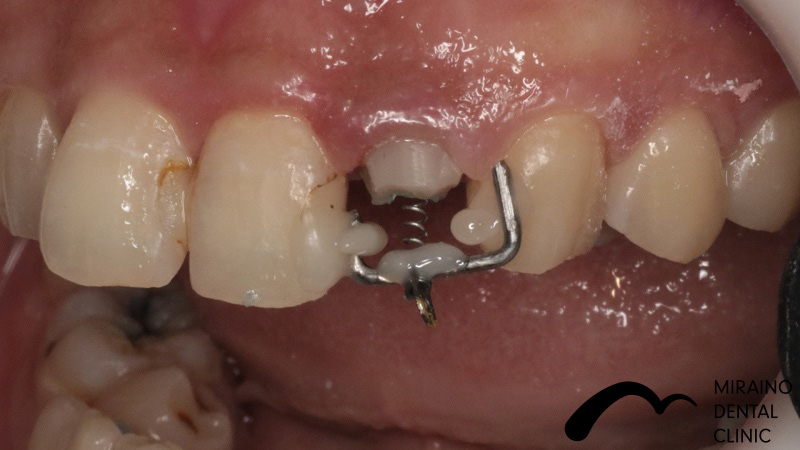

歯の破折予防:MTMの症例

| 施術名 | 歯の破折予防:MTM |

| 施術の概要 | 前歯の差し歯の色が気になるということで来院されました。 噛んだ時に下の前歯が隠れており、治療した歯をより劣化させやすい噛み合わせ[過蓋伵合]の方でした。 歯を失う原因のうち、ムシ歯・歯周病以外に歯への負担荷重お伝えしましたが、 根本的な噛み合わせの治療は希望されなかったため、 次回再発した際は抜歯となる可能性が高いため、なるべく再発しにくい歯科治療を希望され、 MTMを行ったのちメタルフリークラウンでの歯冠修復行いました。 |

クリックして詳細を表示

| 施術の内容 | ムシ歯や歯が折れておりで感染除去後に健康な歯が歯茎の下まで達する場合は、 通常、抜歯もしくは2年以内の抜歯前提の延命治療になってしまいます。 両サイドの歯に表装置をつけ骨からひっぱり出すことで、 歯根破折・歯冠脱離による抜歯の可能性を回避します。 部分矯正MTM(Minor Tooth Movement)の略で、 このような場合エクストルージョン(伾出)と言います。 |

|---|---|

| 1歯あたりの治療費 | 1歯につき50,000円 |

| 考えられるリスク、副作用[歯科治療] | 治療後、痛みや違和感、出血、腫れ、麻痺などが出る事があります。 |

| 考えられるリスク、副作用[全てにおいて] | 必ずしもご希望通りにならない事があります |

| 考えられるリスク、副作用[麻酔] | 麻酔を行う場合、腫れやむくみを生じる事があります。 |

| 考えられるリスク、副作用[噛み合わせ] | また、歯並びが変わる事により違和感を生じる事があります。 |

| 考えられるリスク、副作用[被せ・仮歯] | 仮歯の期間中は仮歯の部分で噛むと破損する場合があります。 |

| 考えられるリスク、副作用[根の治療] | 治療に際して、根の治療が必要になる場合があります。 |